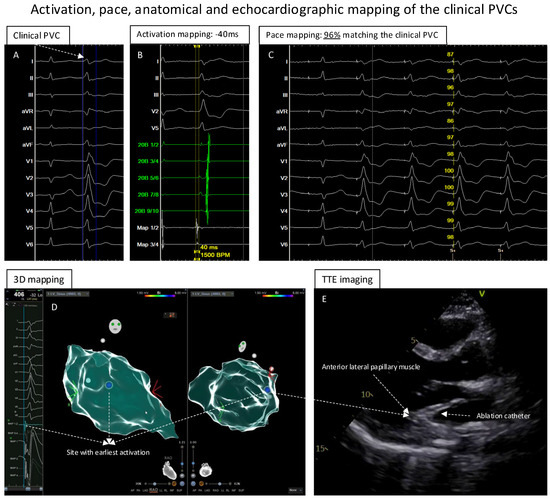

3D Map Combined with Transthoracic Echocardiography for Ablation of Premature Ventricular Contractions/Ventricular Arrhythmia from Papillary Muscle: A Technical Report

2. Methods and Results

Mapping and Ablation of the PVCs